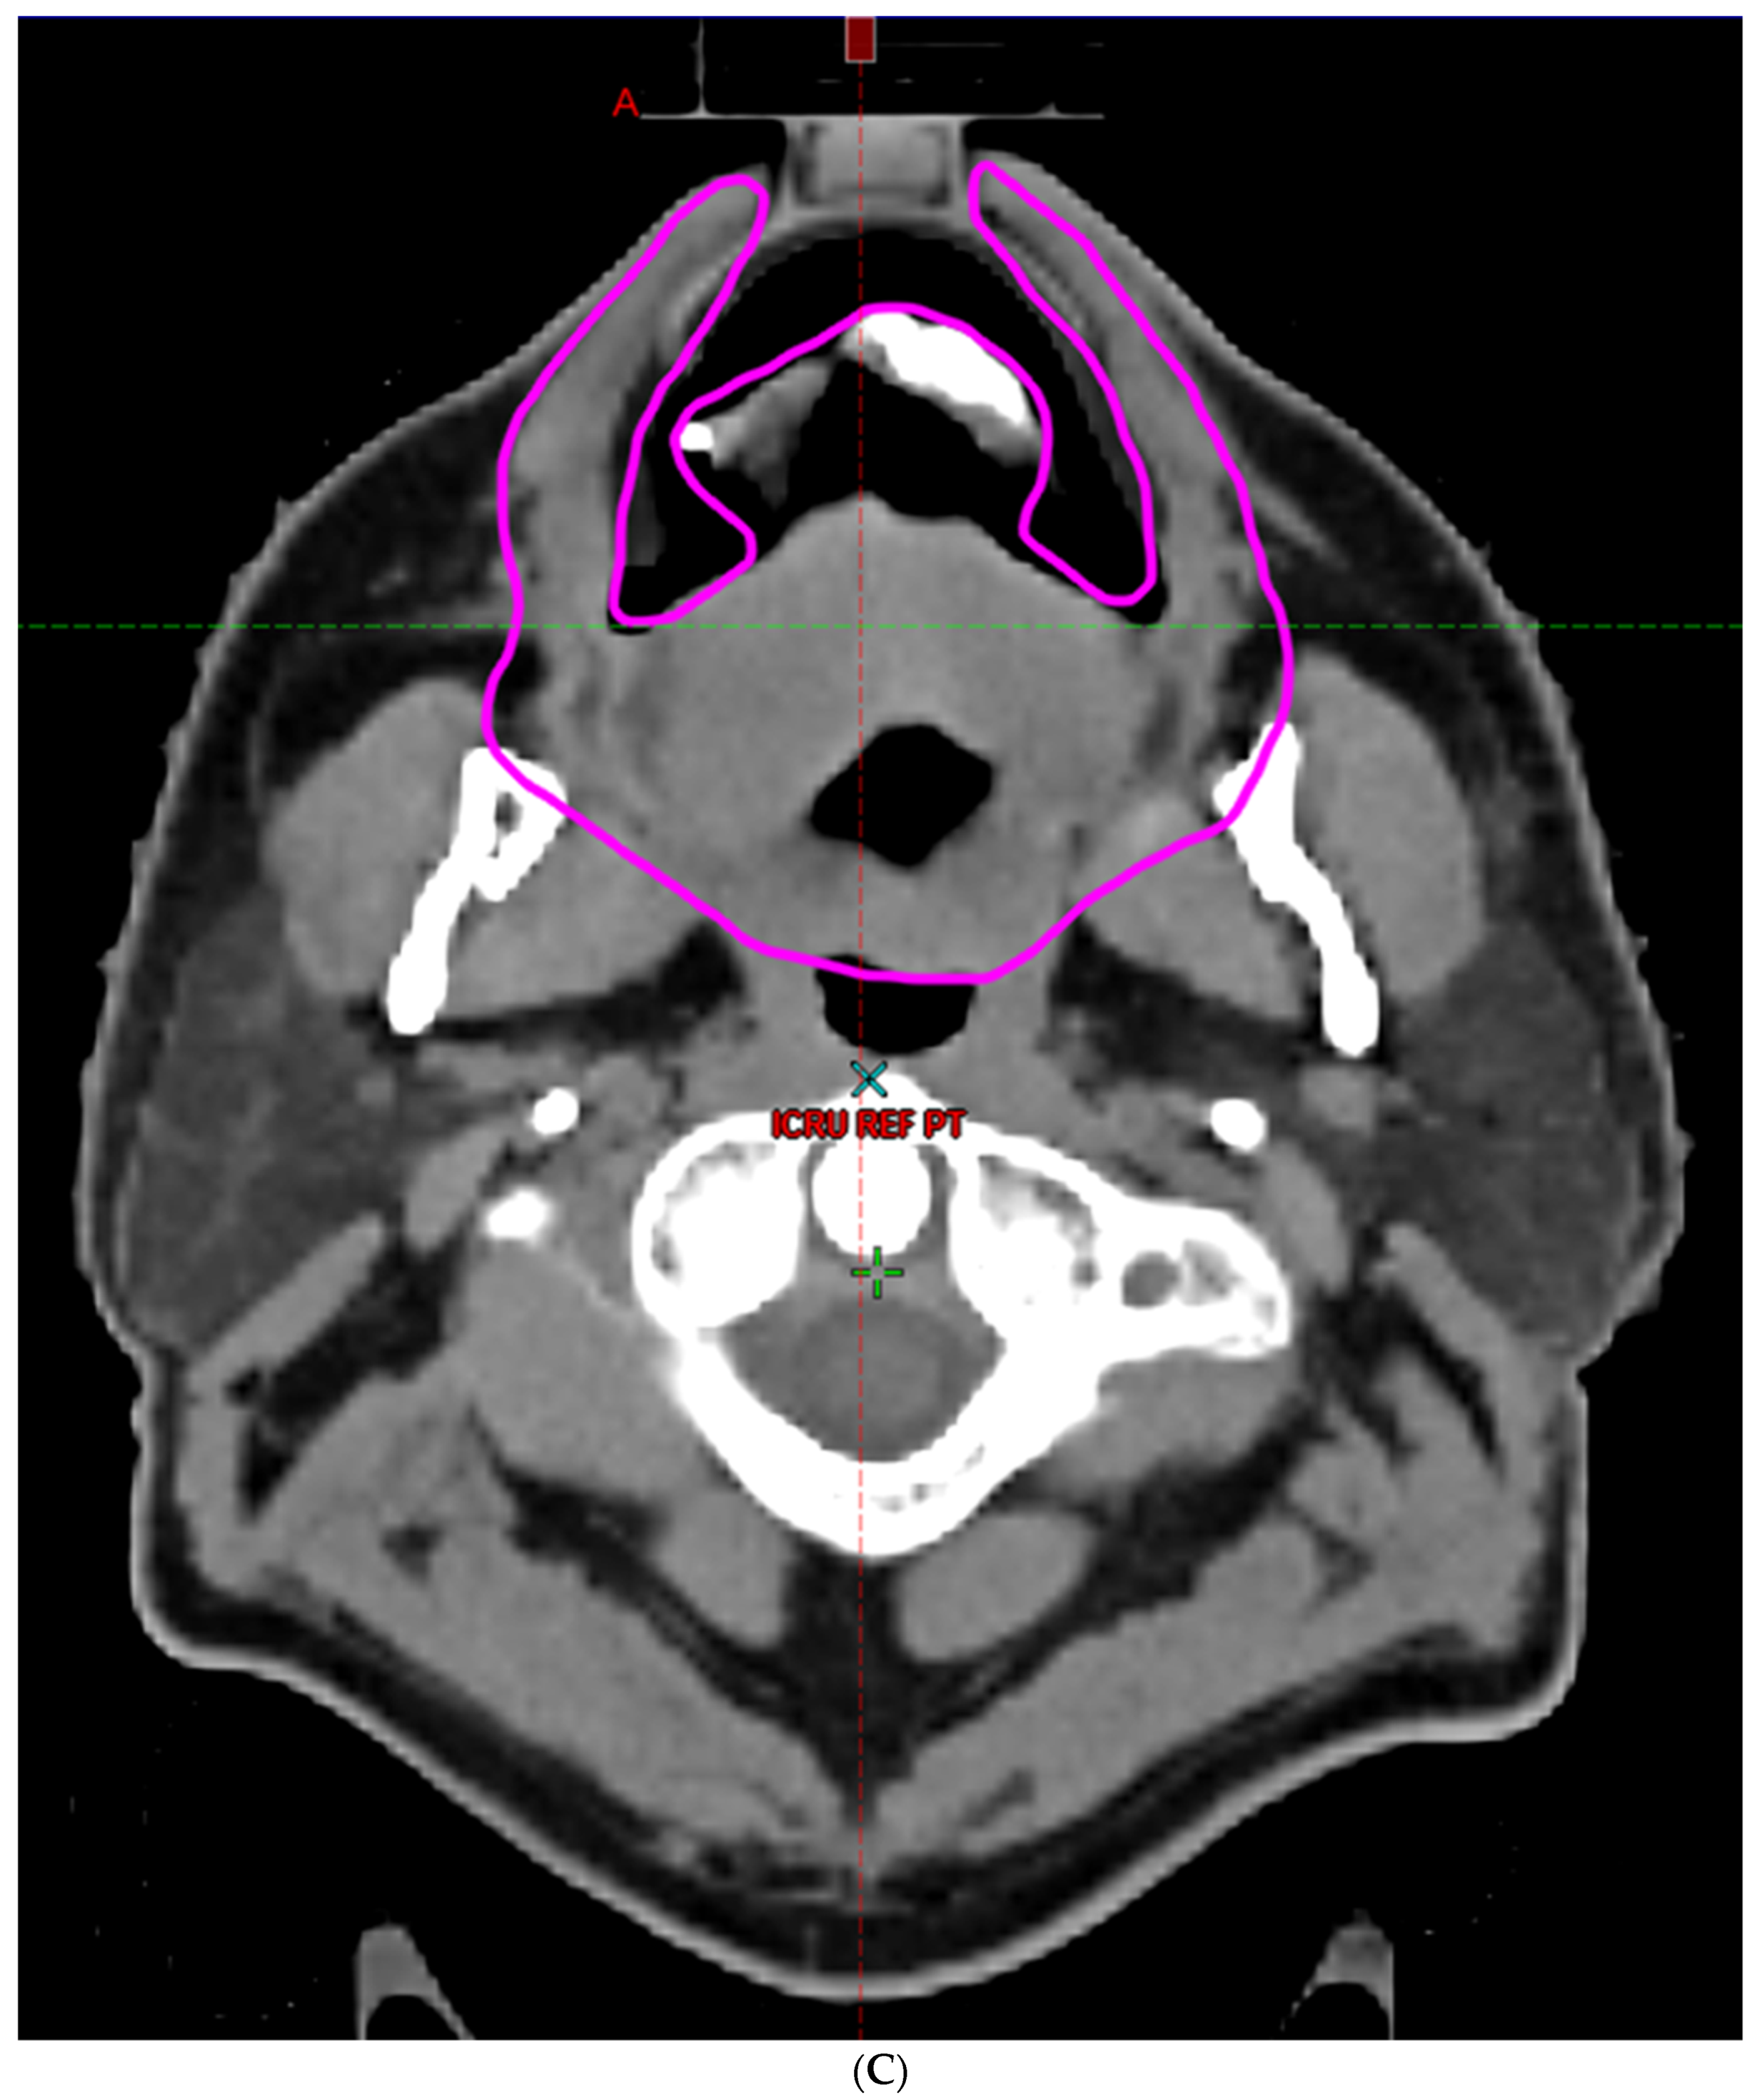

- Hoebers, F.; Yu, E.; Thorstad, W.; O’Sullivan, B.; Dawson, L.A.; Hope, A. A Pragmatic Contouring Guideline for Salivary Gland Structures in Head and Neck Radiation Oncology. The MOIST Target. Am. J. Clin. Oncol. 2013, 36, 70–76. [Google Scholar] [CrossRef]

- Brouwer, C.L.; Steenbakkers, R.J.; Bourhis, J.; Budach, W.; Grau, C.; Grégoire, V.; Van Herk, M.; Lee, A.; Maingon, P.; Nutting, C.; et al. CT-based delineation of organs at risk in the head and neck region: DAHANCA, EORTC, GORTEC, HKNPCSG, NCIC CTG, NCRI, NRG Oncology and TROG consensus guidelines. Radiother. Oncol. 2015, 117, 83–90. [Google Scholar] [CrossRef]

- Li, K.; Yang, L.; Hu, Q.-Y.; Chen, X.-Z.; Chen, M.; Chen, Y. Oral Mucosa Dose Parameters Predicting Grade ≥ 3 Acute Toxicity in Locally Advanced Nasopharyngeal Carcinoma Patients Treated with Concurrent Intensity-Modulated Radiation Therapy and Chemotherapy: An Independent Validation Study Comparing Oral Cavity versus Mucosal Surface Contouring Techniques. Transl. Oncol. 2017, 10, 752–759. [Google Scholar] [CrossRef]

- Sun, Y.; Yu, X.-L.; Luo, W.; Lee, A.W.; Wee, J.T.S.; Lee, N.; Zhou, G.-Q.; Tang, L.-L.; Tao, C.-J.; Guo, R.; et al. Recommendation for a contouring method and atlas of organs at risk in nasopharyngeal carcinoma patients receiving intensity-modulated radiotherapy. Radiother. Oncol. 2014, 110, 390–397. [Google Scholar] [CrossRef]

- Dean, J.A.; Welsh, L.C.; Gulliford, S.L.; Harrington, K.J.; Nutting, C.M. A novel method for delineation of oral mucosa for radiotherapy dose–response studies. Radiother. Oncol. 2015, 115, 63–66. [Google Scholar] [CrossRef]